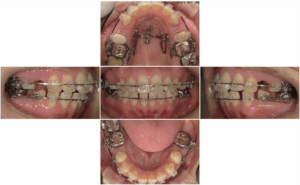

④ 上顎にアイステーション(固定装置)を埋入

矯正開始5か月目に、歯を効率よく動かすための固定源として、上顎にアイステーションを設置しました。

アイステーションがしっかり固定されたら、次は内側にワイヤーが追加される予定です。

⑤ 矯正の経過写真

矯正開始前と最新のお写真を掲載しています。

実際の変化が伝わりやすいので、ぜひご覧ください。

治療途中(現在)